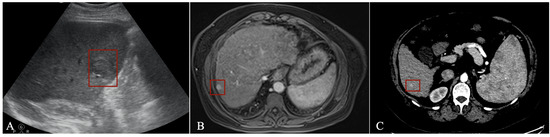

- Tiyarattanachai, T.; Apiparakoon, T.; Marukatat, S.; Sukcharoen, S.; Yimsawad, S.; Chaichuen, O.; Bhumiwat, S.; Tanpowpong, N.; Pinjaroen, N.; Rerknimitr, R.; et al. The feasibility to use artificial intelligence to aid detecting focal liver lesions in real-time ultrasound: A preliminary study based on videos. Sci. Rep. 2022, 12, 7749. [Google Scholar] [CrossRef]